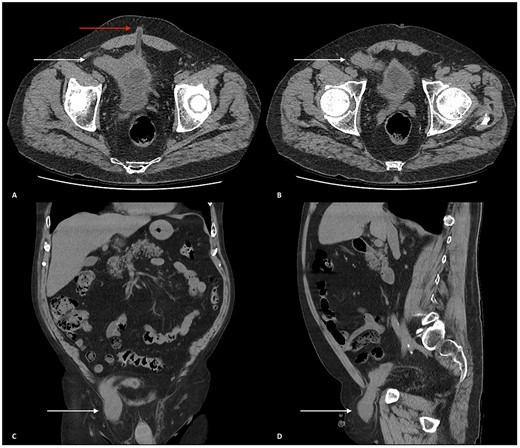

Biochemical results showed a serum sodium of 129 mmol/l, serum creatinine 168 μmol/l (baseline 104 μmol/l) and estimated glomerular filtration rate 33 ml/min/1.73m2. Urinalysis was positive for leukocytes and blood. An abdominal computed tomography (CT) scan with contrast showed an incarcerated right indirect inguinal hernia containing omental fat and a portion of the urinary bladder passing into the scrotum (Fig. 1). The patient received intravenous fluids; his renal function was optimized before he underwent a right open herniorrhaphy with mesh. The patient was discharged 2 days later with no complications.

(A and B) Axial CT scan of the abdomen and pelvis showing the urinary bladder herniating into the right inguinal canal (white arrows). (A) Urinary bladder extending towards the right deep inguinal ring before herniating into the right inguinal canal. An umbilical hernia can also be seen (red arrow). (B) Urinary bladder herniating into the inguinal canal. (C) Coronal CT scan of the abdomen and pelvis displaying the urinary bladder herniating into the right inguinal canal and traversing through the right scrotum (white arrow). (D) Sagittal CT scan of the abdomen and pelvis showing the urinary bladder herniating through the right inguinal canal, through the right spermatic cord and positioned superiorly above the right testicle.